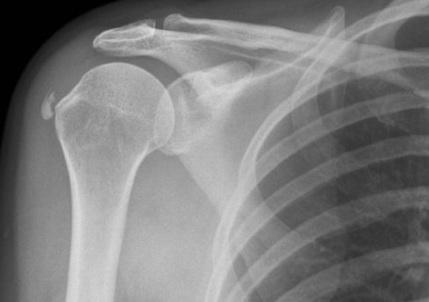

이러한 칼슘은 생기는 위치에 따라 증상이 다를 수 있는데 주로 회전근개의 부착부분에 생기기 때문에, (주로 Supraspinatus)

오구돌기 아래부분의 충돌이 있게 됩니다.